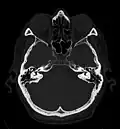

Craniale Computertomographie; links oben: Raycasting (= VR)-Darstellung; rechts oben: transaxialer Schnitt; links unten: multiplanar reformatierter sagittaler Schnitt; rechts unten: multiplanar reformatierter koronaler Schnitt

Erst mit der Einführung von Mehrzeilen-Spiral-CTs Mitte der 1990er Jahre gab es in der Computertomographie isotrope Voxel.[1] Da alle heutigen (2011) klinischen CTs kleine isotrope Voxel erzeugen können, ist eine hohe räumliche Auflösung in beliebigen Raumrichtungen möglich. Durch die multiplanare Reformation werden auch sagittale und koronale Darstellungen in hoher Qualität möglich, die für den Nicht-Radiologen erheblich einfacher zu verstehen sind. Die Maximum Intensitäts Projektion stellt die Maximalwerte aus einem frei wählbaren Datenvolumen dar, die auf eine Ebene projiziert werden, vergleichbar einem Schattenbild. Durch die heute auf Auswerte- bzw. PACS-Workstations preiswert verfügbare Rechenleistung können aus den Daten auch hochwertige 3D-Darstellungen in Form von MIP, Surface-Rendering oder – am aufwändigsten und beeindruckendsten – Raycasting erzeugt werden.